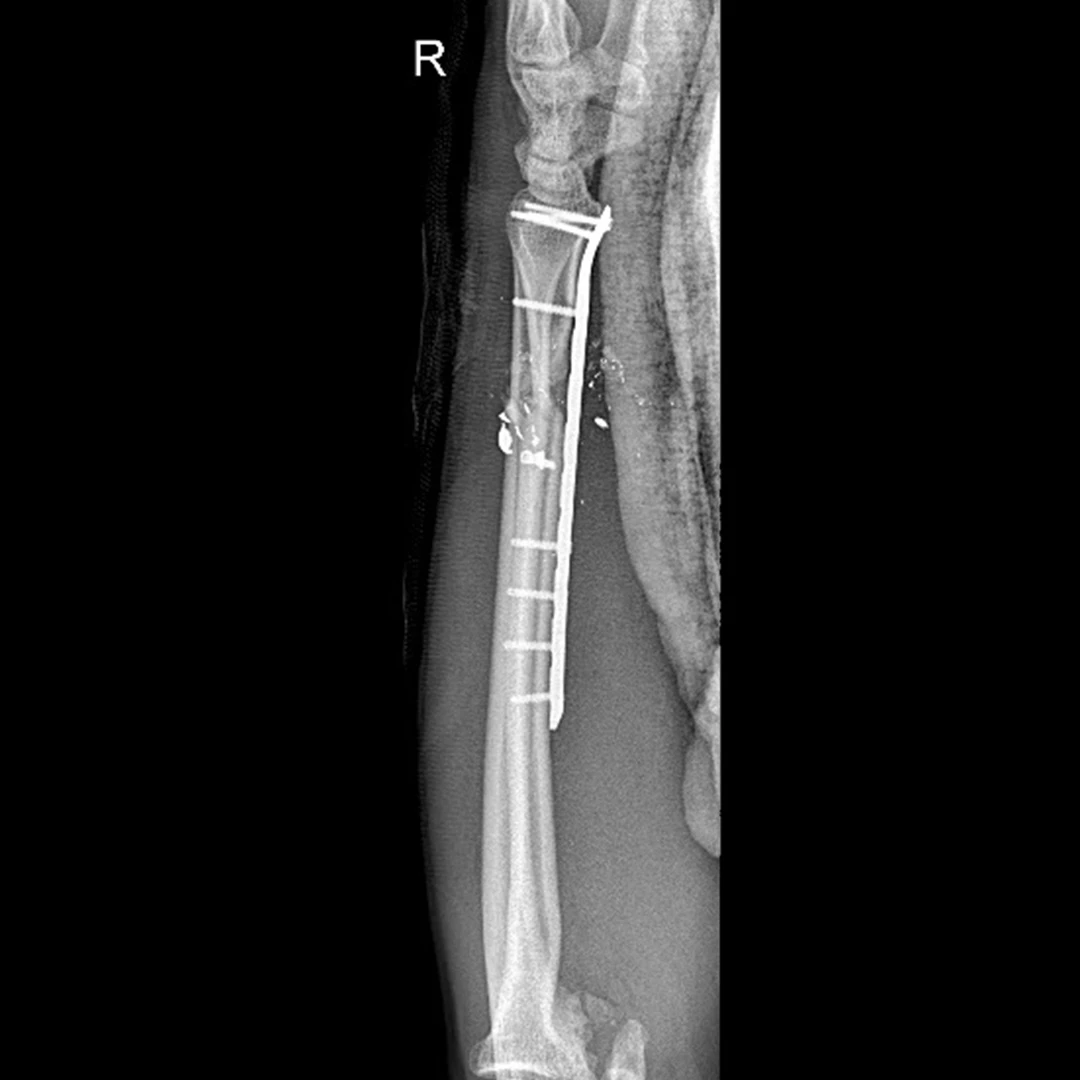

Placas para radio distal

RÁDIX Large

Rádix Plus

Indicaciones

Fracturas en la porción distal del radio simples y complejas

con compromiso intra y extra articular.